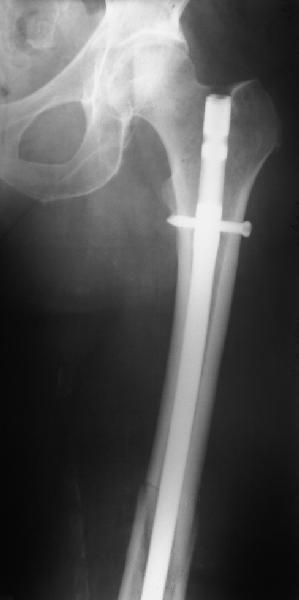

Представляю вам один из наших недавних случаев выполнения малоинвазивного остеосинтеза бедренной кости обычной пластиной 95 градусов. Длина восстановлена с помощью дистрактора (по сути это основная и б(о)льшая часть репозиции). Произведено два небольших доступа, проведена спица направитель. Рентген-контроль для подтверждения достаточной длины/оси (ЭОП использовался в другой операционной). Создание туннеля обратной стороной фиксатора. Поворот фиксатора, введение клинка по спице. Фиксация проксимального и дистального концов пластины.

Получилось очень симпатично, поздравляю и восхищаюсь мастерством.

Хотя закрытый остеосинтез блокированным гвоздем выглядит технически проще, особенно при диафизарных переломах. Не говоря о биомеханических преимуществах внутрикостного имплантата, еще меньшей инвазивности, возможности динамизации при проблемах со сращением... Стоимость гвоздей и пластин сопоставимая, на рынке есть масса отечественных предложений.